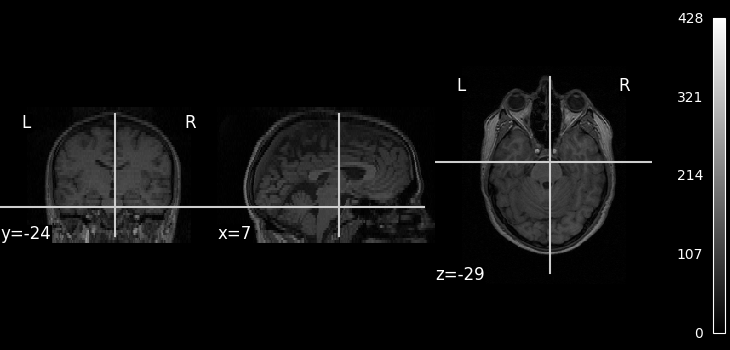

We can display the mean functional image and the subject’s anatomy:

plot_img(mean_img, cbar_tick_format="%i")

plot_anat(subject_data.anat, cbar_tick_format="%i")

show()